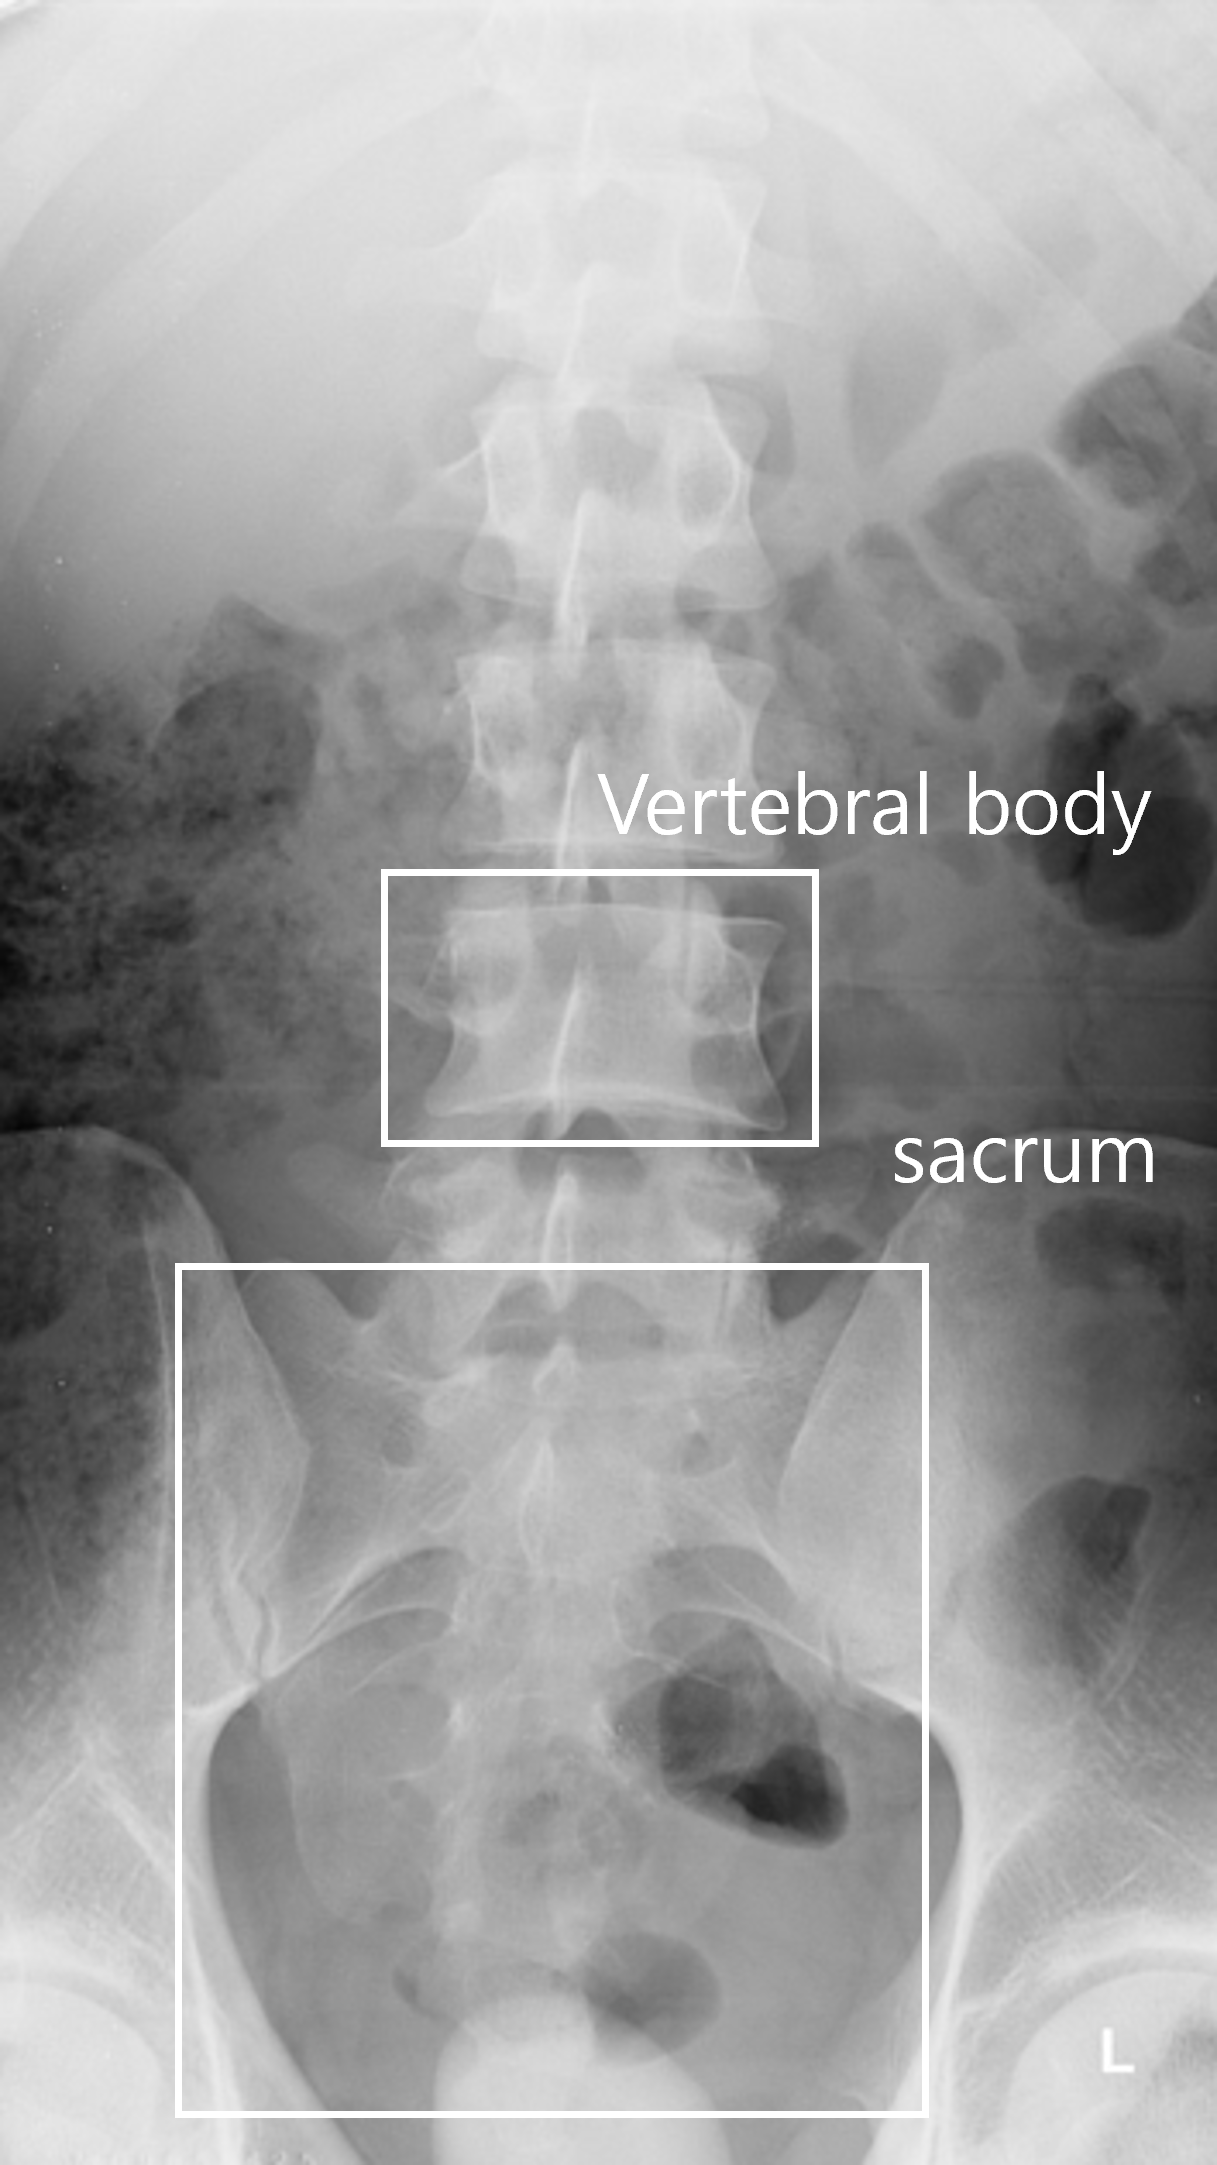

AI 모델이 의료 영상을 효과적으로 학습할 수 있도록, 각 부위와 촬영 방식(AP, Lateral 등)에 맞추어 세그멘테이션(Segmentation), 키포인트(Keypoint), 바운딩 박스(Bounding box) 등 세 가지 방식의 정밀 라벨링 작업을 복합적으로 수행했습니다.

고관절(Hip) 및 무릎(Knee): 대퇴 근위부와 비구 등의 세그멘테이션, tear drop 및 대퇴 골두를 포함한 다수의 키포인트 검출 작업을 진행했습니다.